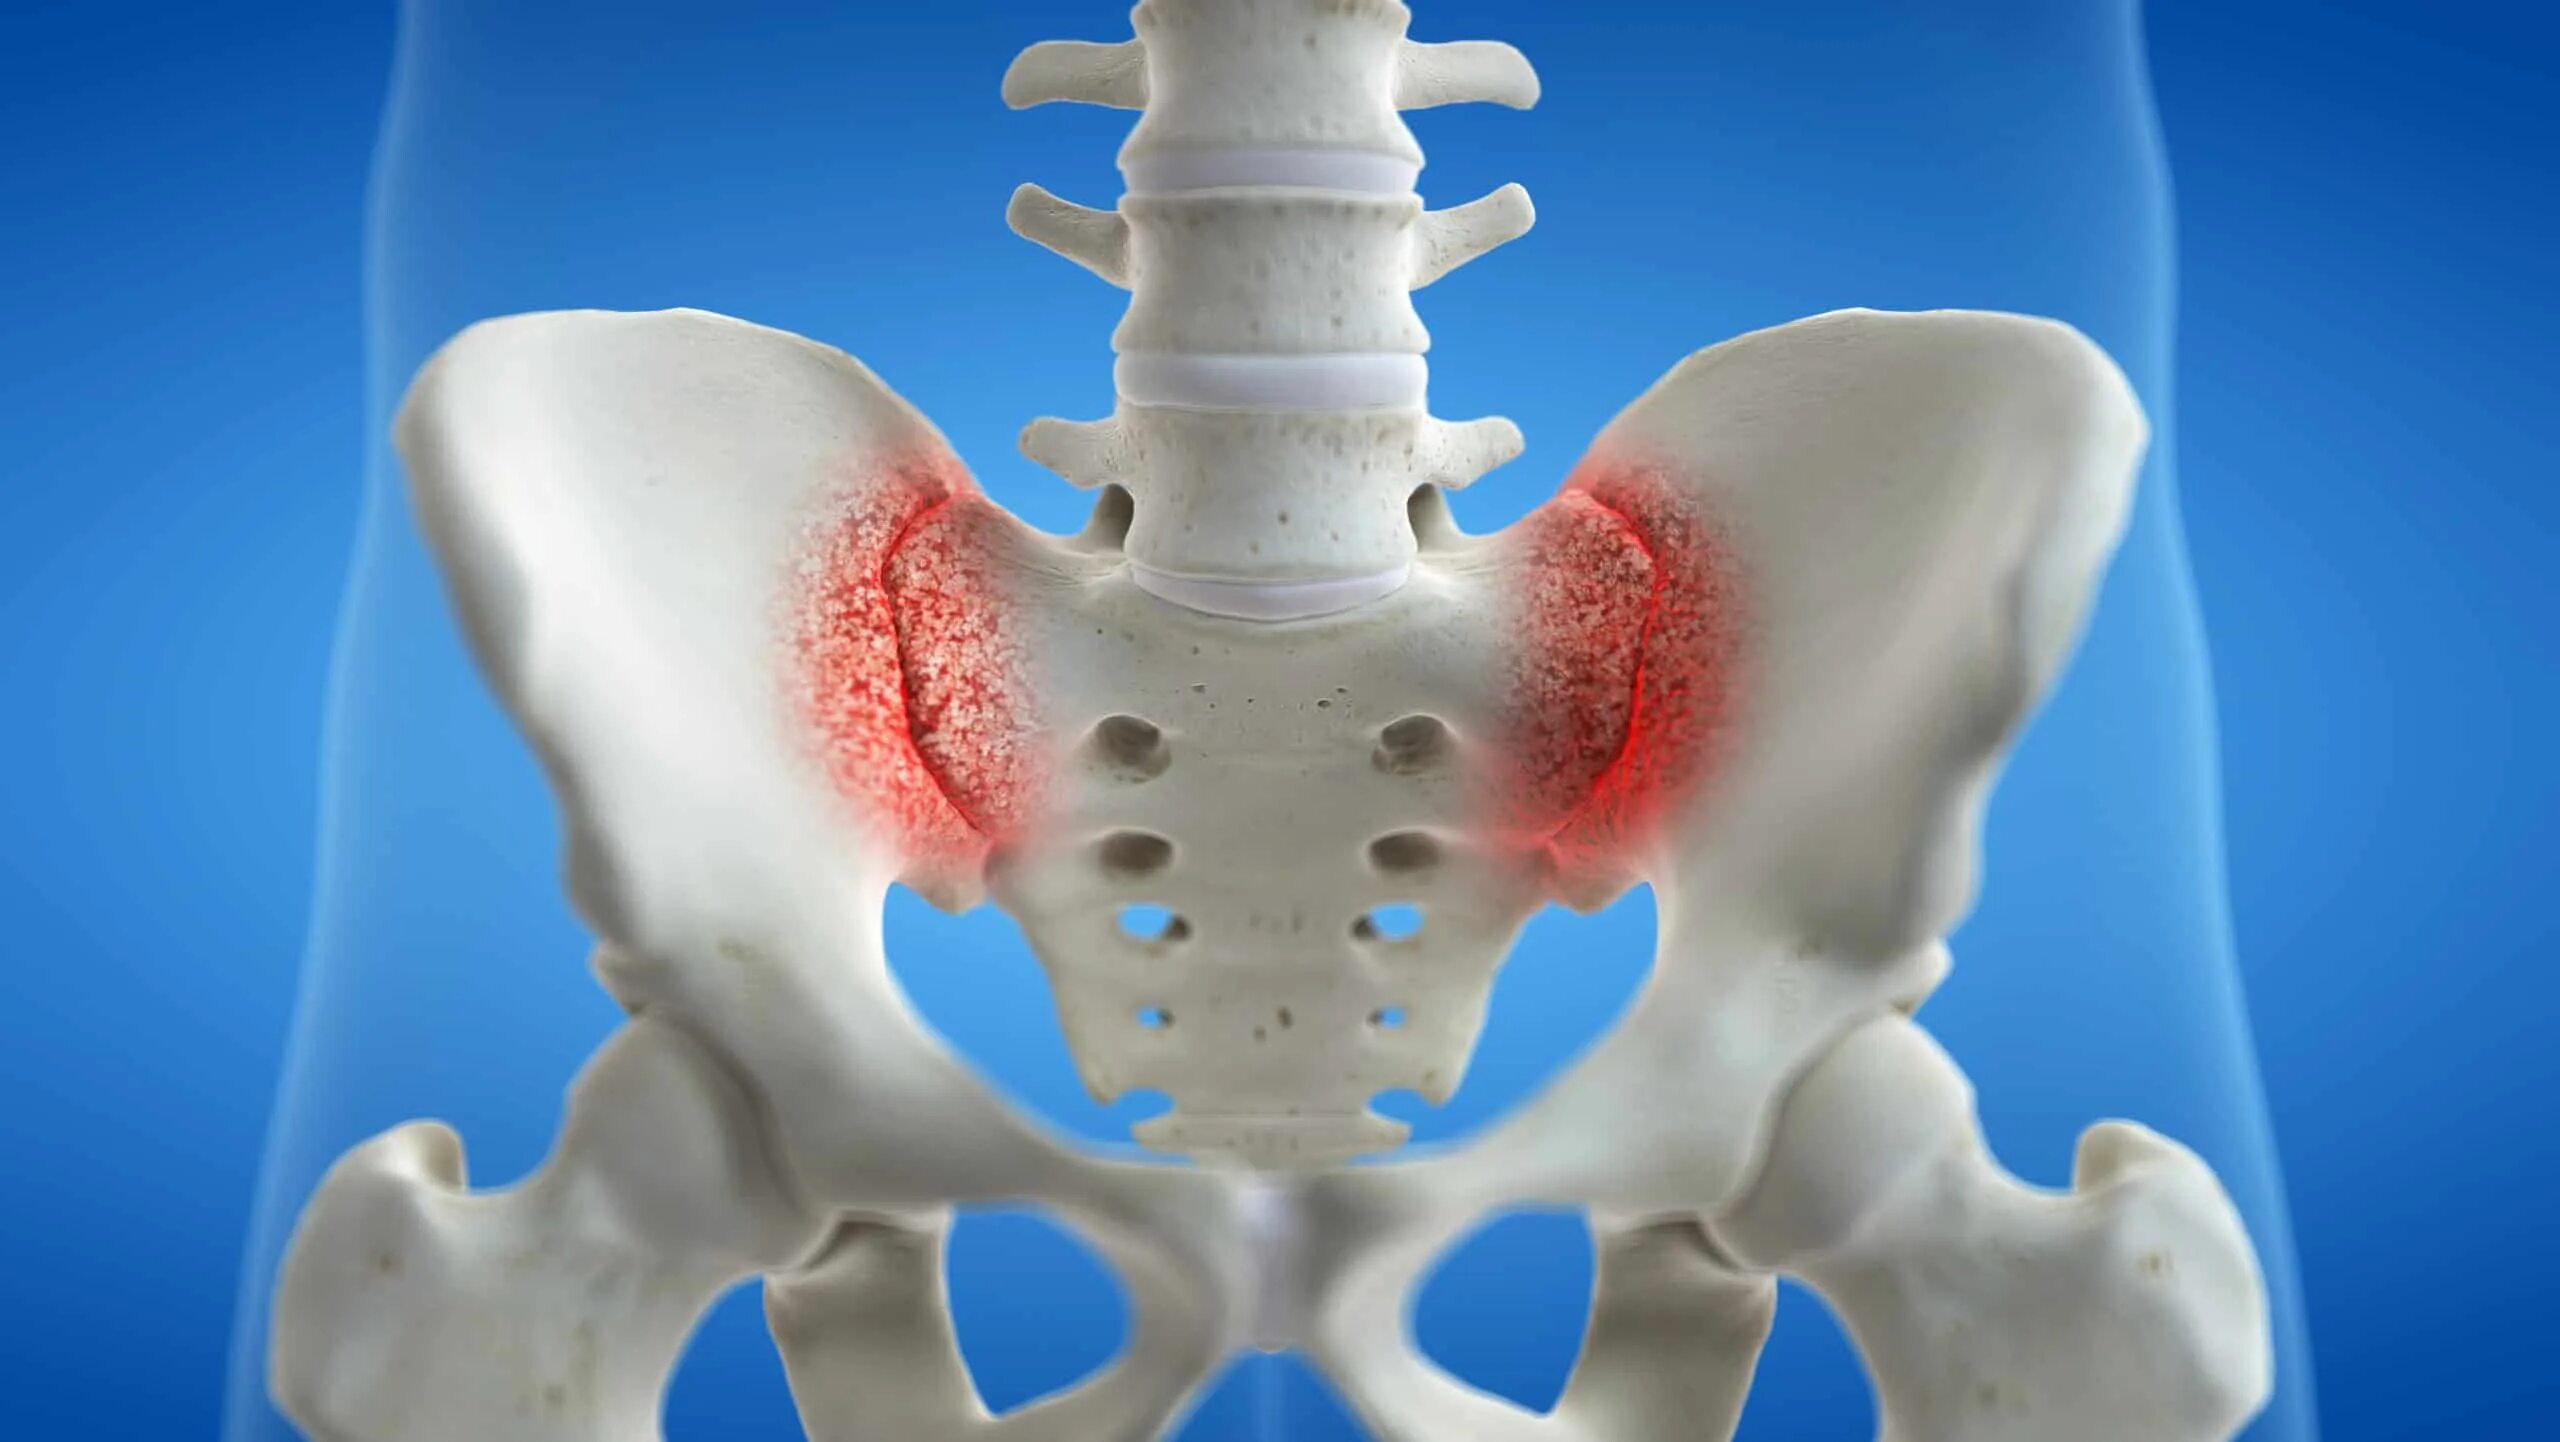

Воспаление подвздошных сочленений